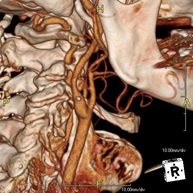

Prova radiològica que consisteix en obtenir imatges de l'os penyal del temporal (oïda interna, mitjana i externa) d'alta definició anatòmica, mitjançant l'ús d'un equip de TC (Tomografia Computeritzada). Indicacions: pèrdua d'audició sobtada o crònica, quadres vertiginosos, mareig, malformacions congènites. - Angio-TC Troncs Supraaòrtics

Prova radiològica que consisteix en obtenir imatges de les artèries caròtides del coll d'alta definició anatòmica, mitjançant l'ús d'un equip de TC (Tomografia Computeritzada) i la injecció de contrast intravenós. Posteriorment, les imatges són reconstruïdes en tres dimensions (3D). Indicacions: accident vascular cerebral agut, accident vascular transitori, buf cardíac. - TC Columna cervical

- Supra-aortic trunk CT angiography

Radiological test that provides high definition anatomical images of the carotid arteries of the neck using CT (Computed Tomography) equipment and the injection of an intravenous contrast agent. The images are then reconstructed in three dimensions (3D). Indicated for: acute cerebral vascular accident, transient vascular accident, carotid bruit.